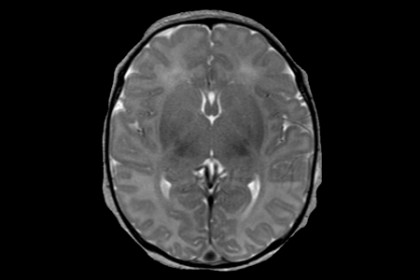

Please understand that our phone lin. SINAPSE Image of the Month: MRI incidental findings â€

These symptoms can run the gamut from mild tingling to more severe vision loss. MRI Uses in MS - YouTube

I presented to my doctor with a second episode of significant vision loss in one eye in a period of five months. An Abnormal Mri Scan of Stock Footage Video (100% Royalty-free) 9891290 | Shutterstock